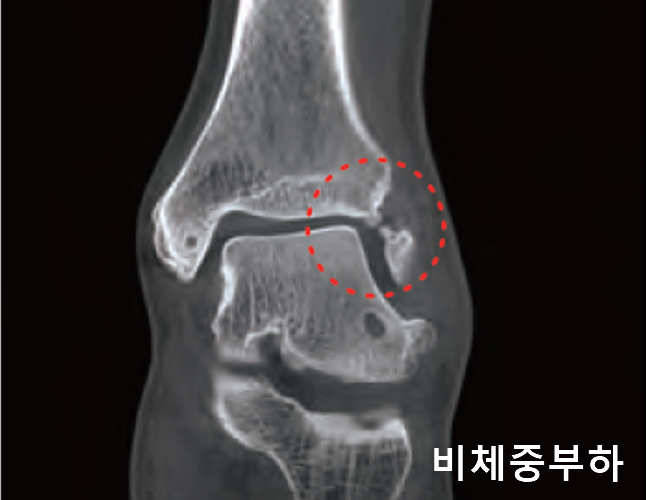

체중이 부하된 상태의 촬영으로 보다 정밀한 진단과 분석

bright WBCT는 체중이 실린 상태에서 촬영함으로써, 비체중부하 상태에서는 확인하기 어려운 다양한 변화를 보다 정확하게 진단하고 평가할 수 있도록 지원합니다.